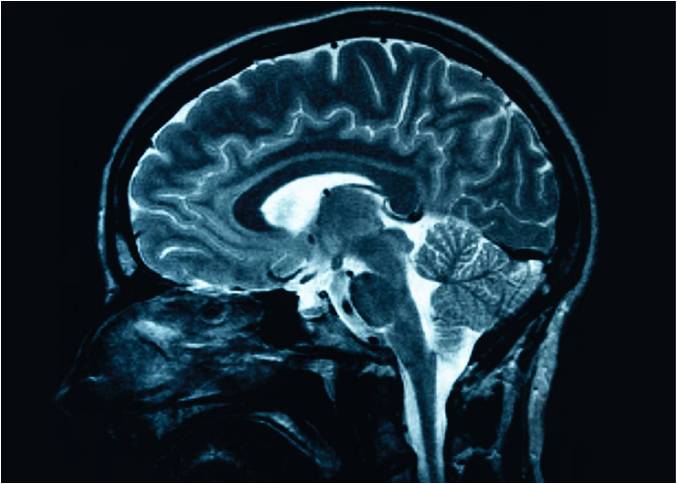

საშიშია თუ არა ტვინის შერყევის შემდეგ ძილი

ხშირად გაიგებთ მოსაზრებას, რომ ადამიანმა, ტვინის შერყევის მიღების შემდეგ არ უნდა დაიძინოს - არის რისკი, რომ ძილი კომატოზურ მდგომარეობაში გადაიზარდოს.